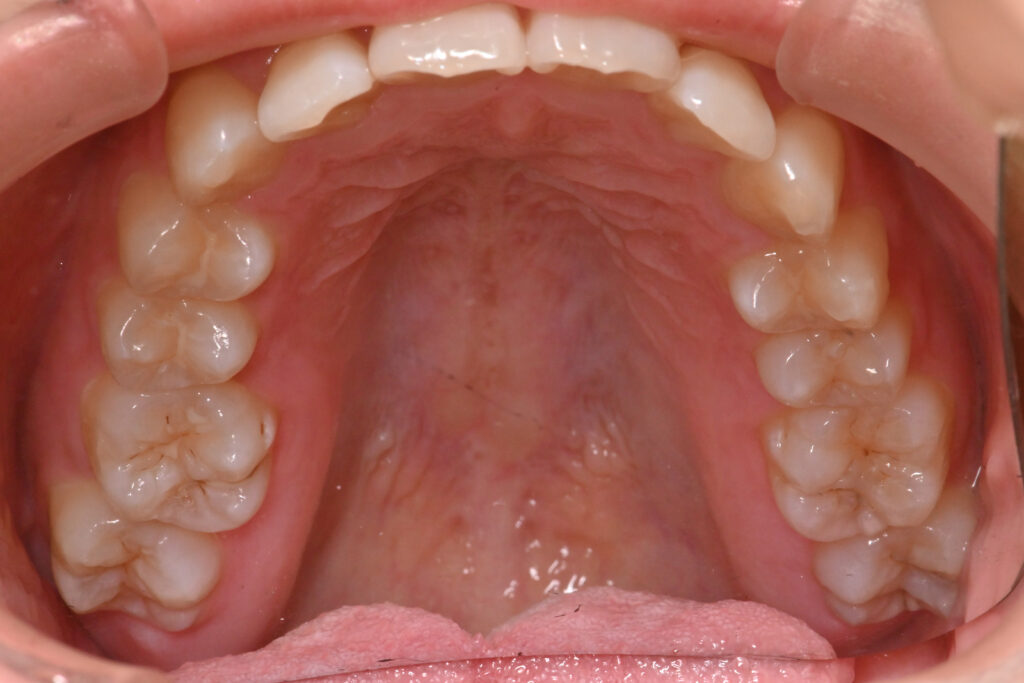

上顎

治療前